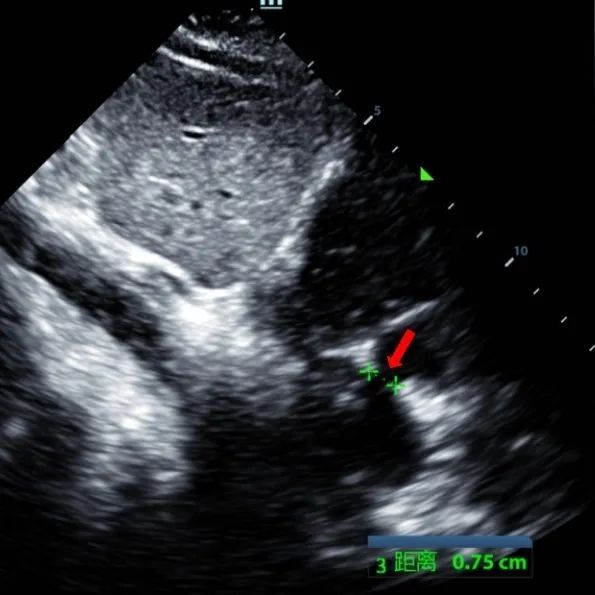

A 9-year-old male with secundum ASD (7.5–7.9 mm) was treated using a MemoSorb BDASD-I 12 mm occluder and 12F delivery system. No complications or comorbidities were noted pre-procedure.

Serial echocardiographic follow-ups showed stable device position and favorable cardiac remodeling. Gradual degradation confirmed the occluder's long-term safety and efficacy.